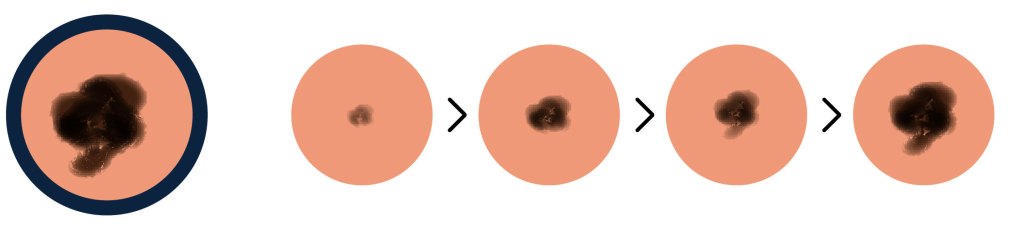

E is for Evolving

The mole is changing in size, shape, or color.

Any of these warning signs should be discussed with a doctor, especially if you feel you are at risk for melanoma.